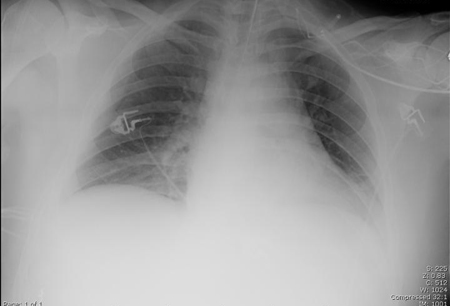

Uma radiografia torácica deve ser obtida no início da avaliação da tosse crônica.[38] Embora não seja diagnóstica das causas mais comuns, os achados podem facilmente desviar a avaliação para causas de maior gravidade como doenças pulmonares estruturais. Eles incluem câncer pulmonar, fibrose pulmonar, tuberculose, bronquiectasia, pneumonia, aspiração e sarcoidose.[Figure caption and citation for the preceding image starts]: Radiografia torácica mostrando hiperinsuflação em paciente com DPOC. A hiperinsuflação é causada pelo componente de enfisema na DPOC, em vez da bronquite crônica subjacente aos sintomas da tosseDo acervo pessoal do Dr. M. A. Sharifabadand, SUNY na Stony Brook School of Medicine, Departamento de Medicina Pulmonar e Intensiva, Mineola, Nova York, e Dr. J. P. Parsons, The Ohio State University Medical Center, Columbus; usado com permissão [Citation ends].